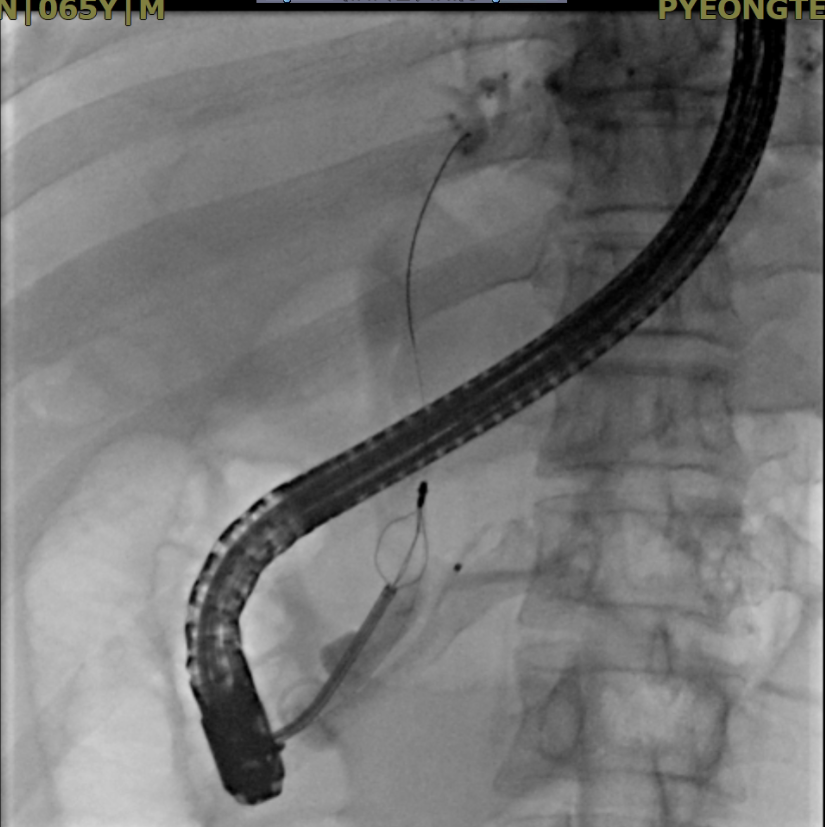

오늘 오후 눈이 노란 황달 환자가 외래로 왔습니다. 저도 인간인지라, 가족과의 저녁식사 시간이 소중합니다. 하지만, 이 환자분의 신체상태와 피검사결과(빌리루빈 정상수치가 1.2 정도인데 이 환자는 10이 넘었습니다.), CT를 종합하였을 때 오늘 저녁에 시술하지 않으면 매우 위험할 것으로 판단되어 ERCP를 오후 늦게 시작하였습니다. 다행히 시술을 잘 되어 담석을 부수는 데 성공하였고 (아래 그림 참조), 회진을 돌 때 환자분은 속이 편안하다고 웃으셨습니다.

단단한 담도의 돌을 부수고 있는 ERCP 시술